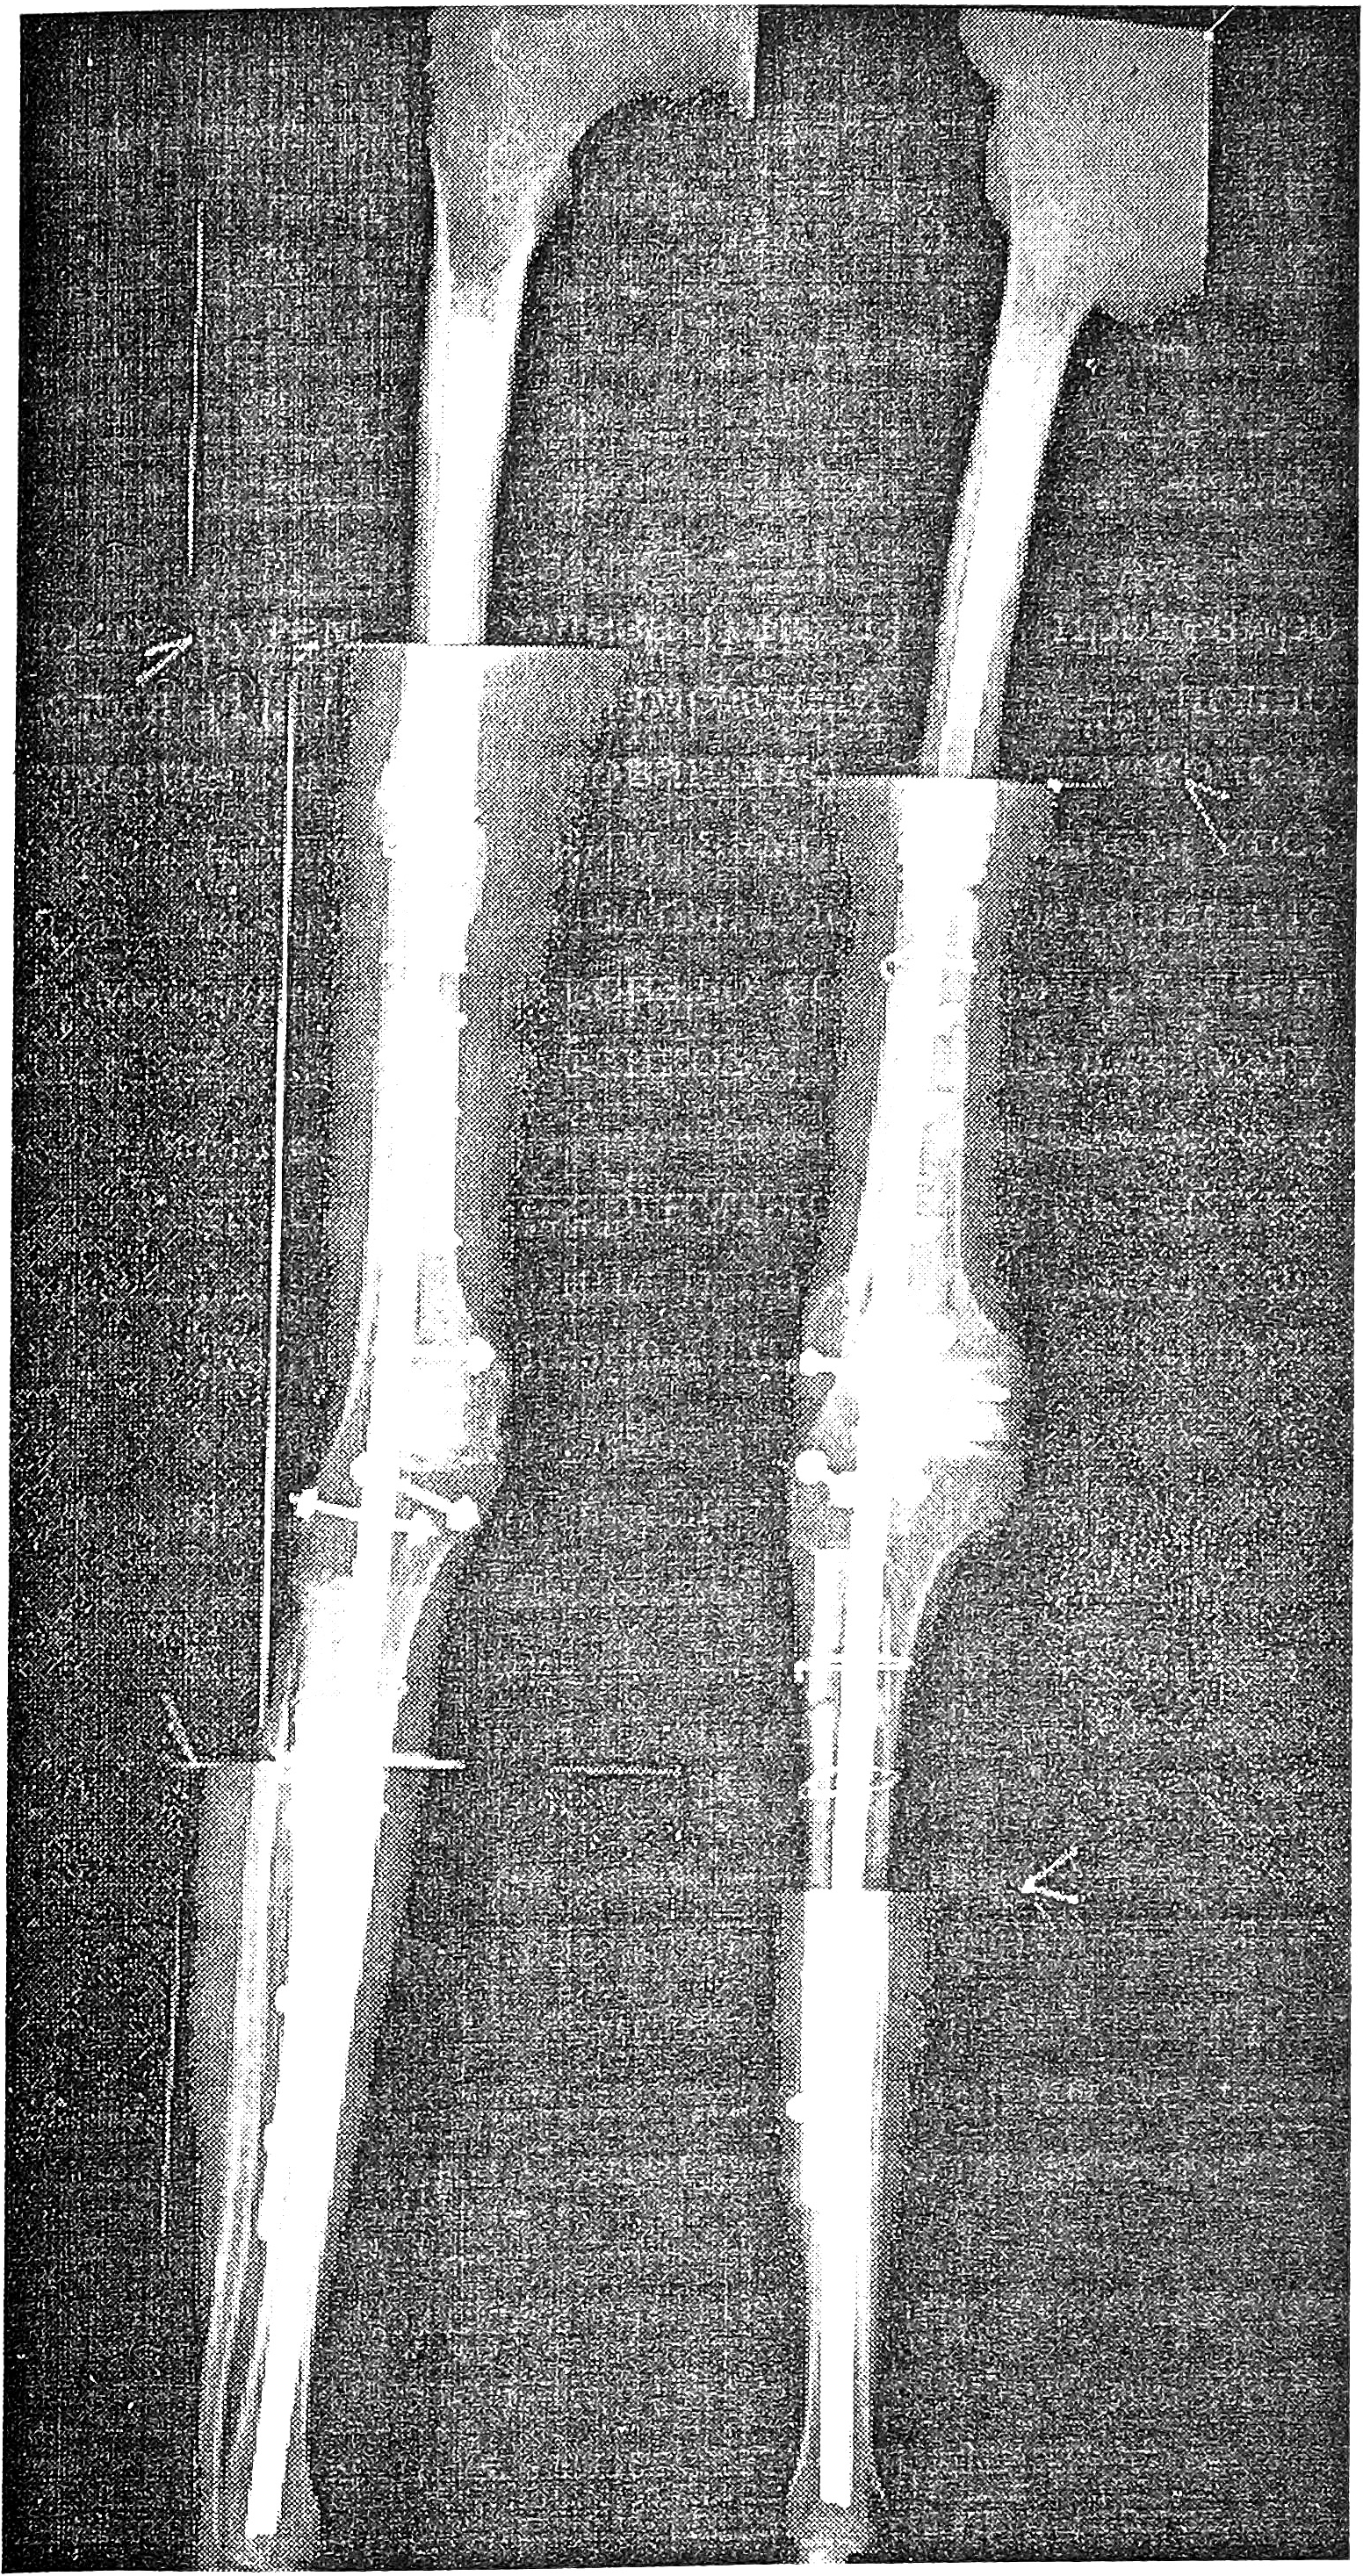

Методам резекции-реконструкции может быть противопоставлена резекция-реимплантация [4], которая позволяет сохранять конечность даже при удалении очень крупных опухолей, циркулярно поражающих весь сегмент. При операциях на нижней конечности используется так называемая поворотная пластика [6], при которой производится резекция цилиндрического сегмента конечности, в большинстве случаев с сохранением только нервов, а затем реимплантация дистального сегмента с реконструкцией сосудов. Поскольку обращенная вперед ступня и укороченная бедренная кость неудобны для протезирования, может быть рекомендован метод J. Borggreve — поворот голени назад на 180°, в результате чего становится возможным протезирование и создание сравнительно активного подвижного «коленного» сустава (рис. 4). Благодаря сохранению ноги у пациента не возникает ощущения ампутации, а кроме того, функциональность конечности существенно выше, чем при ампутации и протезировании бедренной кости.

Рис. 4. Больной 20 лет через 5 лет после ротационной пластики по поводу остеосаркомы дистального конца правой бедренной кости: вид сбоку без протеза и функция правой ноги с протезом.